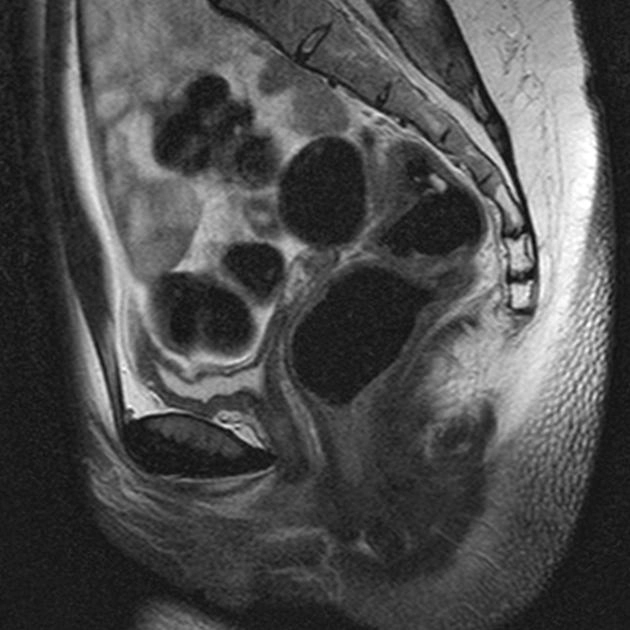

Tử cung có vách ngăn (Septate uterus)